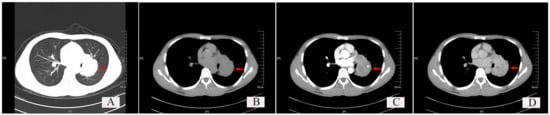

Figure 3. Chest CT findings of a typical solitary fibrous tumor (SFT) of the lung. (A) Lung window: Red arrow shows a well-demarcated soft tissue density shadow, which is nodular and located at the hilum, with regular morphology. (B) Plain scan of the mediastinal window: the red arrow indicates the tumor. (C) Arterial phase scan of the mediastinal window: red arrow indicates the tumor. (D) Venous phase scan of the mediastinal window: red arrow indicates the tumor.

The typical chest CT findings showed a regular and well-demarcated soft tissue density mass, which could be nodular (Figure 3, red arrow), and the surrounding lung tissue and bronchi were compressed and narrowed. SFTs occurred most frequently in the hilar area or near the visceral pleura. The maximum diameter of the mass varied from 0.7 cm to 23 cm, with a larger SFT (5.0 × 4.0 × 4.0 cm) of one case occupying two lobes of the lung. Most cases of SFTs were in the range of 1–10 cm, accounting for 88.46% (46/52), only two cases of SFTs were less than 1 cm, and four cases of SFTs were over 10 cm.

Early in SFT development, patients often have no obvious symptoms. SFTs are often accidentally found by thin-layer CT of the chest during physical examinations. As tumors develop, cough, chest tightness, chest pain, shortness of breath, and other symptoms appear. CT often shows regular and well-demarcated soft tissue density mass, which are nodular, sometimes peripherally lobulated. However, imaging manifestations of SFTs lack specificity and heterogeneity is possible; sometimes, SFTs may be misdiagnosed as other tumors [7]. The radiographic findings reported in this study are consistent with this report. The tumor size of most SFTs ranges from 1 to 10 cm. The maximum diameter of SFTs of the lung in this study varied from 0.7 to 23 cm; most cases of SFTs were in the range of 1–10 cm, accounting for 88.46% (46/52), and only two cases of SFTs were less than 1 cm, with four cases of SFTs over 10 cm.